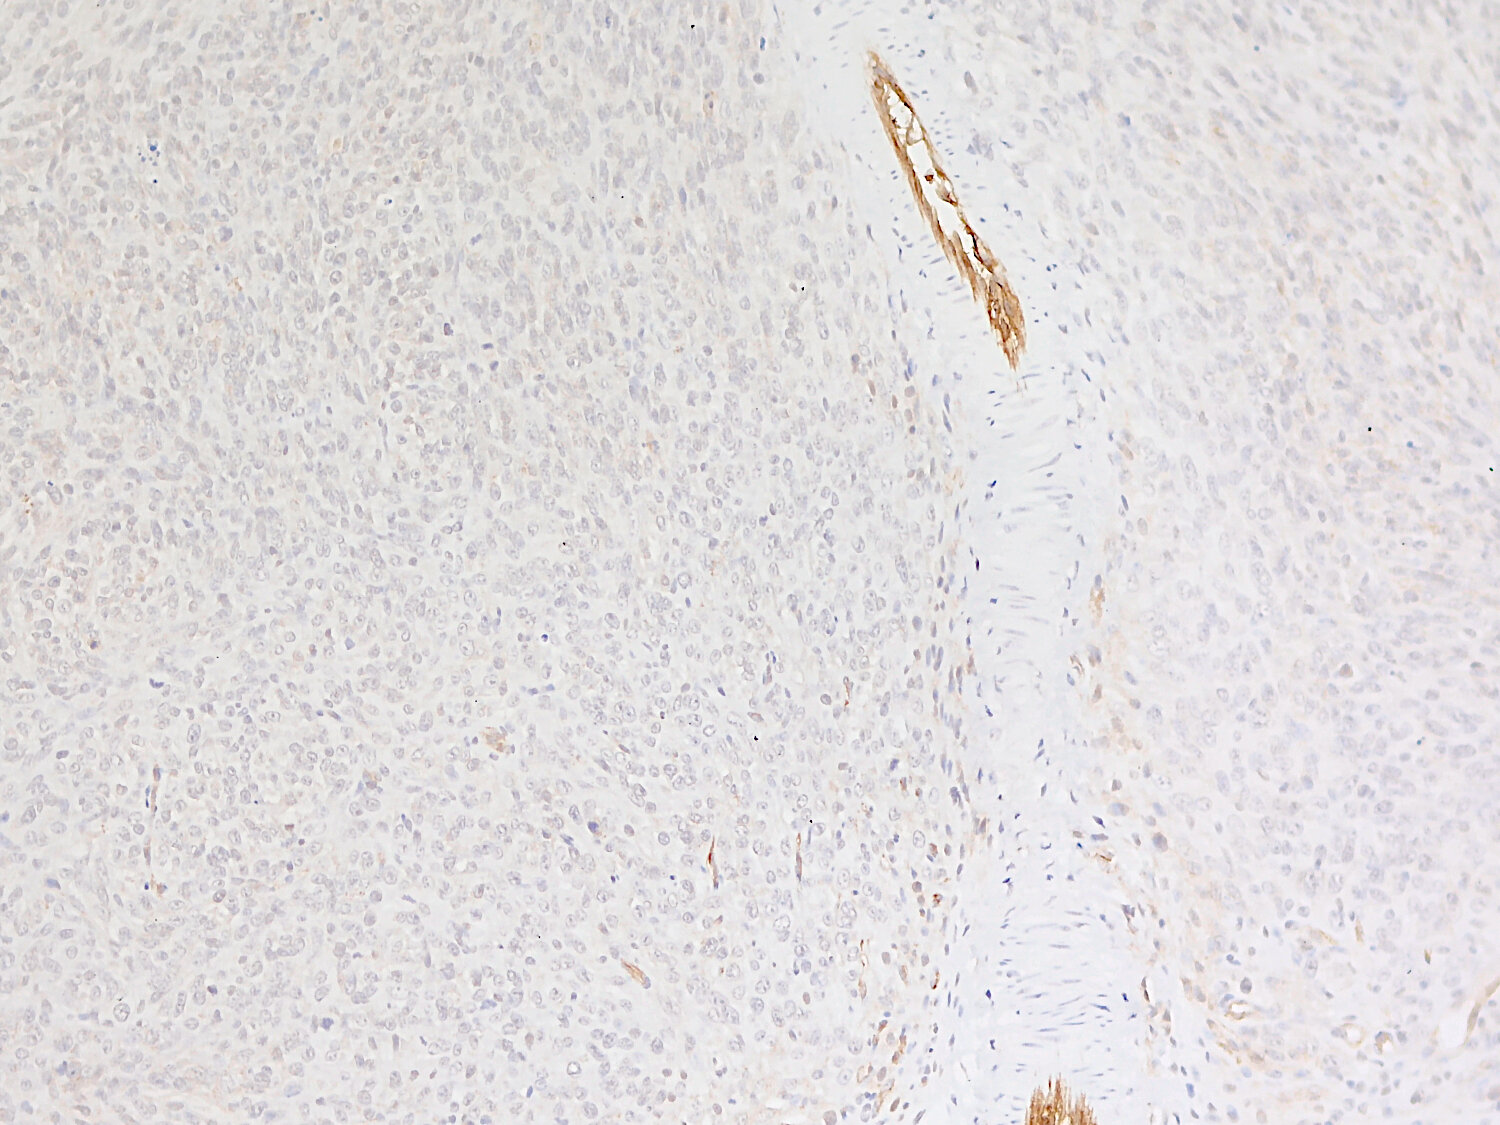

IHC: 1 : 500 (see remarks) gallery

Immunohistochemistry (IHC) on 4% PFA perfusion fixed tissue with 24h PFA post fixation. Immunoreactivity is usually revealed by fluorescence or a chromogenic substrate. Some antibodies require special fixation methods or antigen retrieval steps. For details, please refer to the ”Remarks” section.

IHC: Antigen retrieval with citrate buffer pH 6 is required.

Increased VCAM1 expression in a mouse liver infected with Toxoplasma (T.) gondii